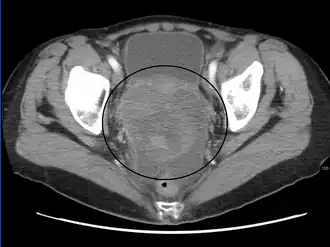

A CT scan shows a solid mass in the pelvis in stage I without yet established blood vessels and septa

The preliminary diagnosis begins with a pelvic examination, serum tumor marker test and imaging. Physicians may feel a large palpable mass or lump in lower abdomen upon insertion of the gloved fingers into the vagina. To further identify the histologic subtypes of OGMTs, blood samples of patients are collected to analyse the serum level of biomarkers released by the tumor cells. A surge in the plasma levels of human chorionic gonadotropin and alpha-fetoprotein is indicative of OGMTs.[1] Lactate dehydrogenase, alkaline phosphatase and cancer antigen 125 might potentially increase as well.[19] To visualize the location and morphology of the tumor, transvaginal ultrasonography is usually employed.[1] The most characteristic appearance is a parenchymal-like heteroechoic mass with sharp borders and high vascularization.[1] Computed tomography would produce stacked image inside the peritoneal region of the body to visualise the lobular pattern of the tumour.[1] Usually for dysgerminoma, solid mass being compartmentalized into lobules with enhancing septa may be evident for haemorrhage or necrosis.[1]